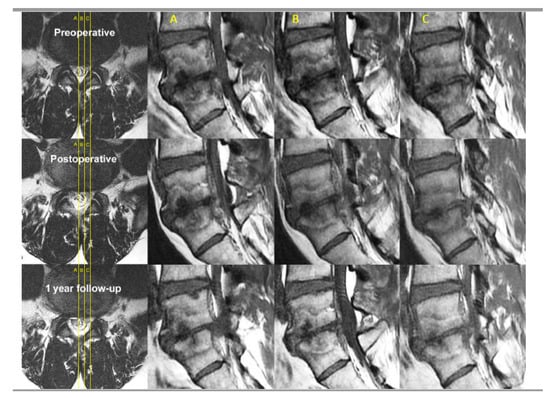

- Kim, H.S.; Adsul, N.; Yudoyono, F.; Paudel, B.; Kim, K.J.; Choi, S.H.; Kim, J.H.; Chung, S.K.; Choi, J.-H.; Jang, J.-S.; et al. Transforaminal Epiduroscopic Basivertebral Nerve Laser Ablation for Chronic Low Back Pain Associated with Modic Changes: A Preliminary Open-Label Study. Pain Res. Manag 2018, 2018, 6857983. [Google Scholar] [CrossRef] [PubMed]

- Modic, M.T.; Steinberg, P.M.; Ross, J.S.; Masaryk, T.J.; Carter, J.R. Degenerative disk disease: Assessment of changes in vertebral body marrow with MR imaging. Radiology 1988, 166, 193–199. [Google Scholar] [CrossRef]